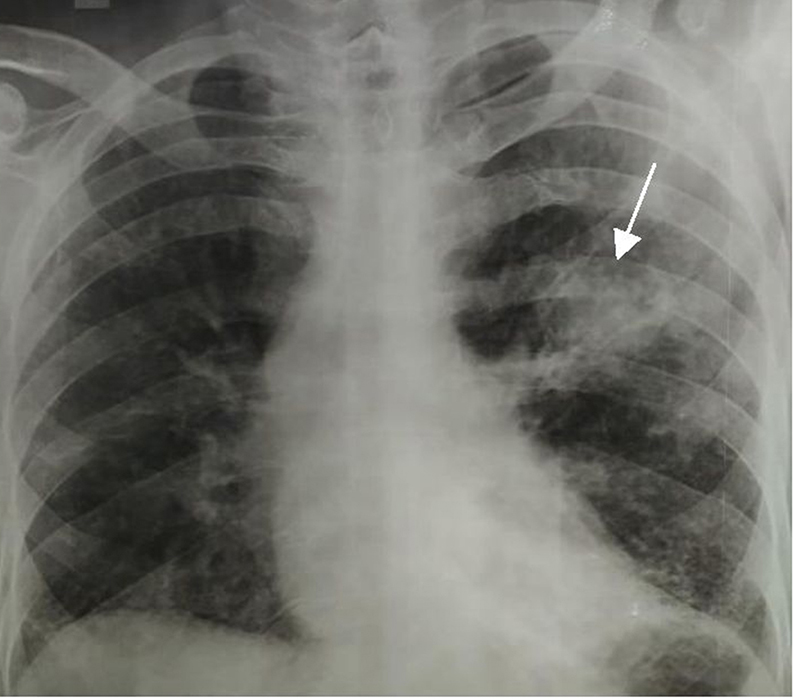

Ziel Nelson stain, a nucleic acid amplification test, and liquid culture were negative for AFB. Review of the serial x-rays over the previous 9 months (Figure 1) showed a cavity in the left mid zone in which the wall progressively increased in size and thickness (Figure 2). Contrast-enhanced computed tomography (CECT) of the chest during the eighth month of treatment revealed a nonspecific interstitial pneumonia (NSIP) pattern with a non-communicating cavity (a large necrobiotic nodule) with a soft tissue collection along its wall (Figure 3A) and collection of soft tissue in the cavity (Figure 3B). Chest x-ray taken 2 months later (tenth month since anti-tubercular treatment initiation) at the institute showed the presence of an air crescent in the same cavity (Figure 4). In view of his history of small joint pains, the patient was worked up for rheumatoid arthritis. Investigations revealed a strongly positive RF and ANA; however Anti-CCp was negative. Total IgE (543 IU/ml), serum specific IgE (3.29 KUA/L) and IgG(>80IU) for Aspergillus fumigatus were high. A diagnosis of RA with ILD with cavitating rheumatoid nodule containing an aspergilloma was made.

Figure 4

Figure 4. Arrow showing “Air-crescent” due to Fungal ball at month 10.